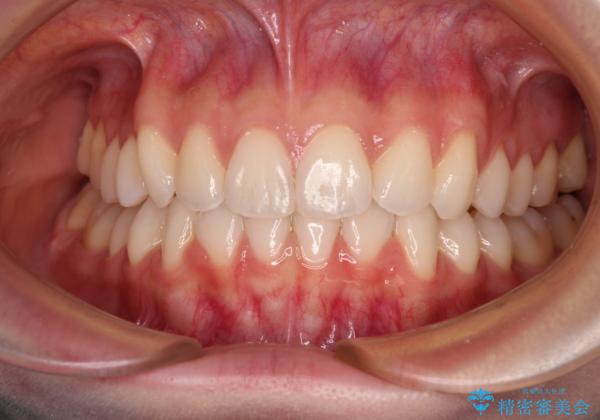

前歯のデコボコと深い咬み合わせ インビザラインできれいに改善

- 前歯のデコボコと下の前歯が隠れてしまう咬み合わせを気にして来院された患者様です。

インビザラインによる上下歯列の拡大と、IPR(歯と歯の間を削る)にるスペースの獲得により、口元のデコボコとディープバイトを改善することとしました。

インビザラインは、装着していない時間がどれだけ短いかが、治療期間を大きく左右します。こちらの患者様は1日22時間以上、毎日欠かさず装着してくださったため、1年弱という短期間で満足のいく歯列に整えることができました。